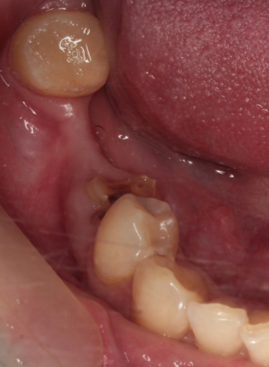

通常抜歯後、顎の骨は吸収する。後のインプラント治療が不利になる。抜歯前の疾患により歯を支える骨を失っており、即時埋入が難しい場合に行っている。

48歳女性